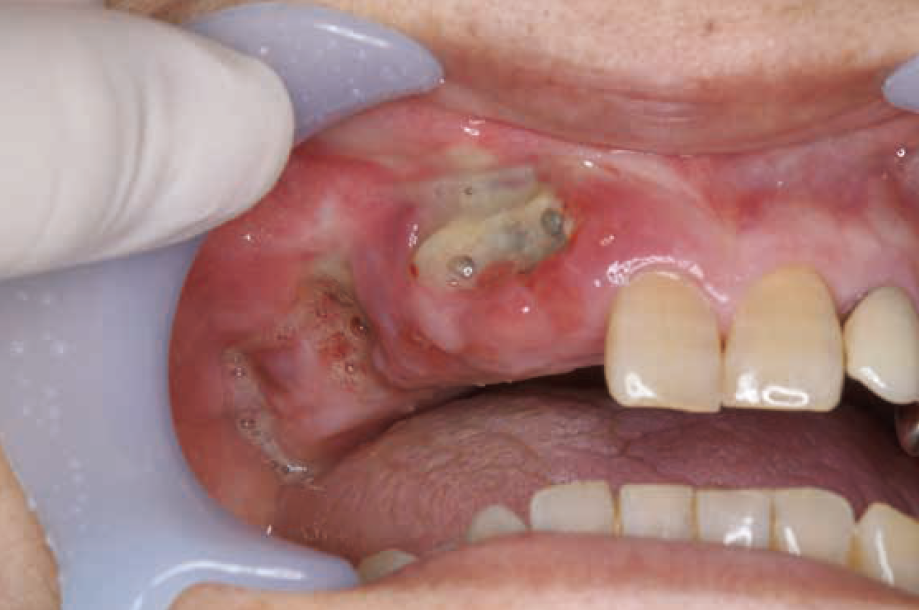

初診時:口腔内写真

右上2~右上6にかけての歯肉の発赤と腫脹を認め、自発痛ならびに圧痛を自覚していた。右上2,3部・右上5部、右上6部の3箇所に骨露出を認め、持続的な排膿を認めた。露出していた歯槽骨(腐骨)に動揺は認めなかった。